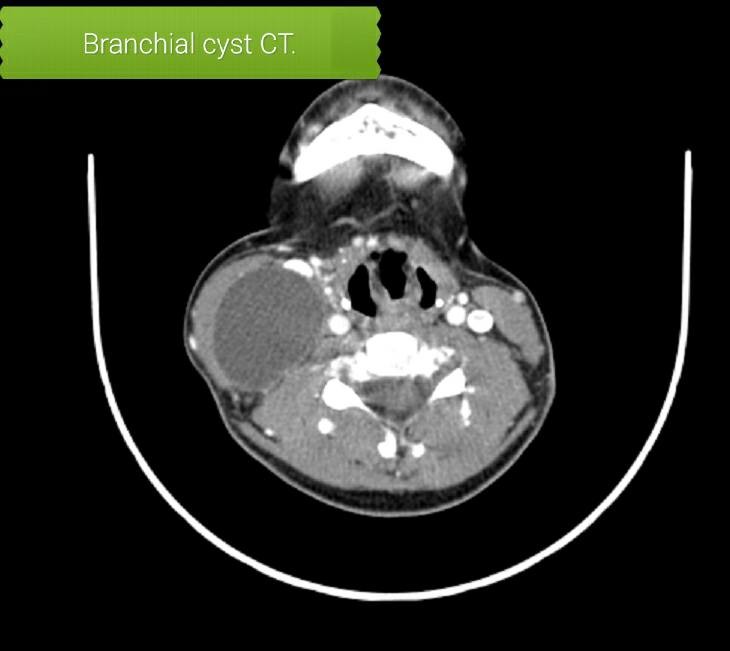

Branchial cyst type II - 1 week post operation - images